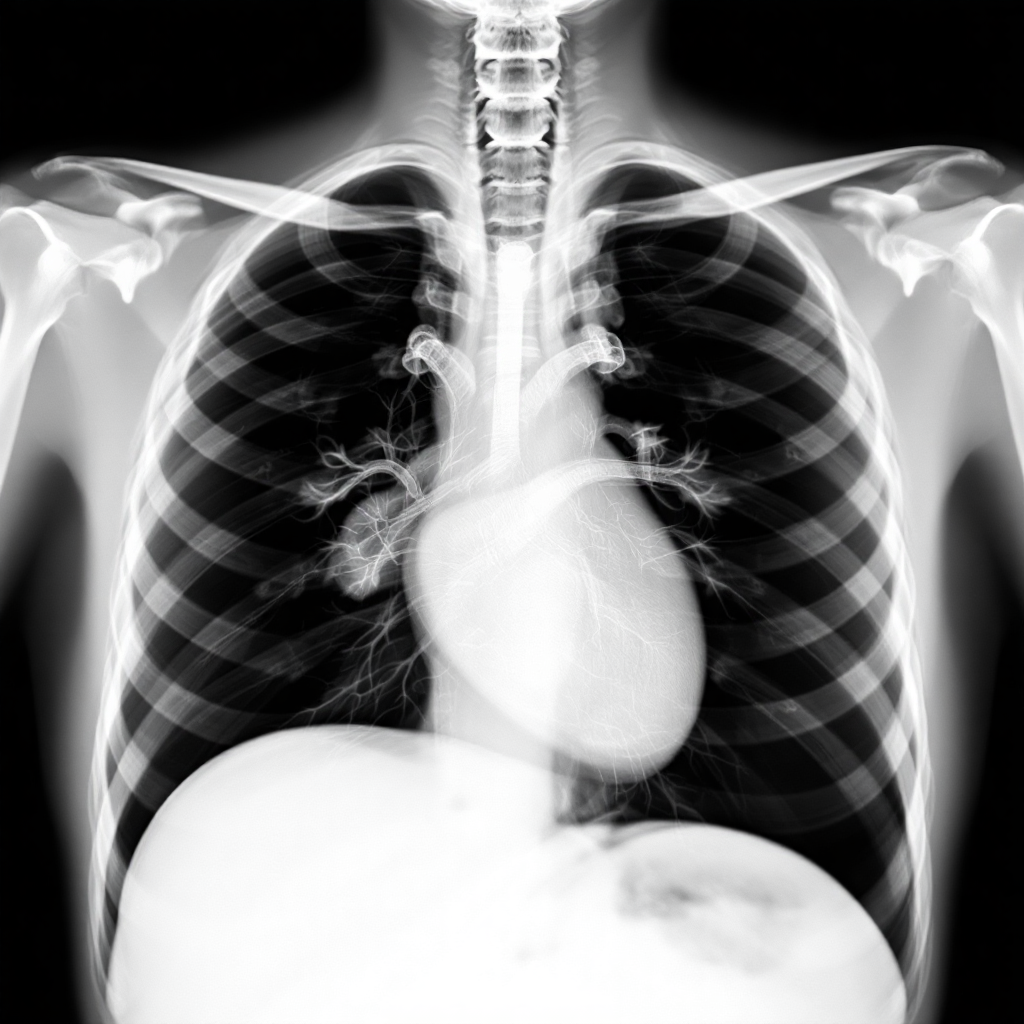

흉부 X-ray 판독 결과를 이해하는 것은 일반인에게는 쉽지 않은 일이에요. 하지만 기본적인 내용들을 알아두시면 의사 선생님의 설명을 더 잘 이해할 수 있어요. 먼저 정상 소견부터 알아보면, '양측 폐야 clear', 'Heart size normal', 'No active lung lesion' 같은 표현들이 나오면 특별한 이상이 없다는 뜻이에요. 이런 경우 안심하셔도 되지만, 정기적인 건강검진은 계속 받으시는 것이 좋아요.

만약 이상 소견이 발견되면 어떤 의미인지 궁금하실 텐데요. 'Pneumonia'는 폐렴을 의미하고, 'Pleural effusion'은 흉막에 물이 찬 상태를 말해요. 'Cardiomegaly'는 심장이 커진 것이고, 'Pneumothorax'는 기흉으로 폐에 구멍이 생겨 공기가 새는 상태예요. 이런 용어들이 나왔다고 해서 너무 당황하지 마시고, 담당 의사와 충분히 상담을 받으시는 것이 중요해요.

판독 결과에서 자주 나오는 'Old healed lesion'이나 'Calcified granuloma' 같은 표현들은 예전에 앓았던 염증이 치유되면서 남은 흔적을 의미해요. 이는 대부분 문제가 되지 않는 소견이지만, 정확한 판단을 위해서는 의사와 상담이 필요해요. 또한 'Follow up recommended' 라는 표현이 나오면 추후 경과 관찰이 필요하다는 뜻이니까, 권장하는 시기에 맞춰 재검사를 받으시는 것이 좋아요.